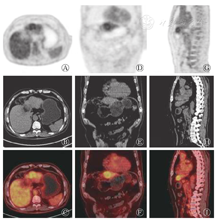

本研究获得我院伦理委员会批准(批准号:201708093),患者于检查前签署了知情同意书。18F-FDG PET/CT采用德国西门子Biograph mct-64,患者空腹6h以上,空腹血糖水平低于10 mmol/L,静脉注射18F-FDG 4.0×109 Bq/kg,安静状态下休息60 min后行18F-FDG PET/CT显像(图2)。图像显示:肝左外叶上段结节,18F-FDG代谢稍增高,SUVmax为2.8,病灶与邻近肝实质分界模糊,难以确定病灶性质。次日行18F-氟代脱氧胸腺嘧啶(18F-fluoro-3′-deoxy-3′-L- fluorothymidine,18F-FLT)显像(图3),图像提示:肝左叶病灶代谢活跃,SUVmax为11.2,病灶与邻近正常肝实质代谢差异明显,高度怀疑肝癌。

18F-FDG PET/CT imaging of the liver (male,69 years old)